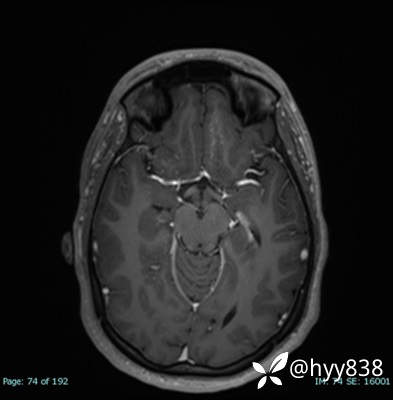

CE